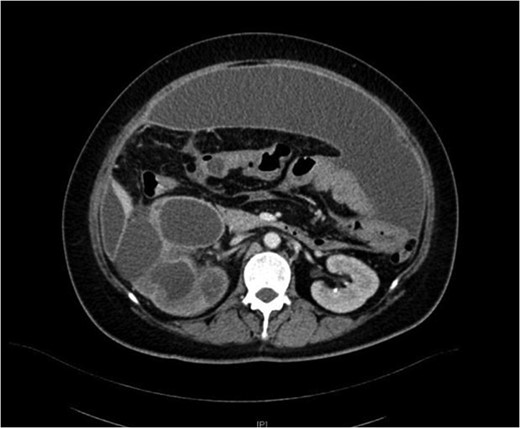

Xanthogranulomatous pyelonephritis (XGPN) is a rare form of chronic pyelonephritis with progressive loss of renal function. Commonly, obstructing urinary calculi are seen. It is difficult to differentiate between XGPN and malignancy in many cases, and the diagnosis is usually only confirmed post-operatively upon histopathological examination of the specimen. Surgical treatment is often the main treatment modality due to suspicion for malignancy. Here, we present a case of XGPN that presented with abdominal distension, which was eventually discovered to be due to a preperitoneal abscess.

She underwent insertion of a right percutaneous nephrostomy drain, percutaneous drainage of the anterior abdominal collection, as well as a percutaneous biopsy of the right renal soft tissue lesion. Urine cultures from the percutaneous nephrostomy grew Proteus mirabilis. Fluid cytology from the abdominal collection showed acute inflammatory cells. Biopsy of the renal lesion showed xanthogranulomatous inflammation.

After a period of antibiotic treatment, she underwent open right nephroureterectomy with exploration, drainage and washout of the preperitoneal collection. During surgery, 1 l of pus was drained from the preperitoneal space, and cultures grew P. mirabilis. The ureter was ligated below the level of the calculus and removed together with the kidney. Final histopathology results showed XGPN with no evidence of malignancy in the kidney or peritoneal lining.

Our patient had an atypical presentation with abdominal distension and presumed ascites, which was eventually revealed to be an anterior preperitoneal collection secondary to infection. Although the initial suspicion was that of a malignant process complicated by ascites, subsequent cytology and histopathological results showed that it was likely benign. In view of the non-functioning renal unit and significant abdominal collection, she underwent definitive surgery.

The most common urinary pathogen identified was Escherichiacoli [3], and common areas of involvement were the retroperitoneum and psoas muscle. In our patient, the retroperitoneal space was surprisingly not greatly involved, but rather it was the anterior preperitoneal space that had significant adhesions and inflammation. The pathogen identified from both nephrostomy and preperitoneal collection was P. mirabilis, showing that both pathologies were linked.